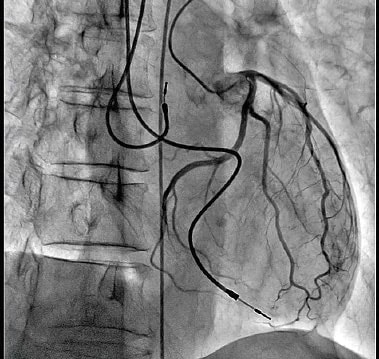

The video image was about five seconds long and had been brought in by Kazuhiro Mori, the FPD/Application Group Manager, and Mitsuru Umeda, the CVS Group Manager in the R&D Department of the Medical Systems Division. It showed a heart with a blood vessel circled around it and also a stent that was expanding the blood vessel. It was the raw image, before image processing was applied, and it included noise throughout the image that made the blood vessel appear fuzzy. Consequently, the location of the blood vessel and of the wire that was inserted through it, was unclear.

Contrast Enhanced Image of Left Coronary Artery Acquired Using the New Trinias Series Equipped with the SCORE PRO Advance Image Processing EngineMorita and Ryo Takeda, a third-year employee under Morita continued trial and error efforts day after day. Then one day, several months later, Takeda happened to mutter.